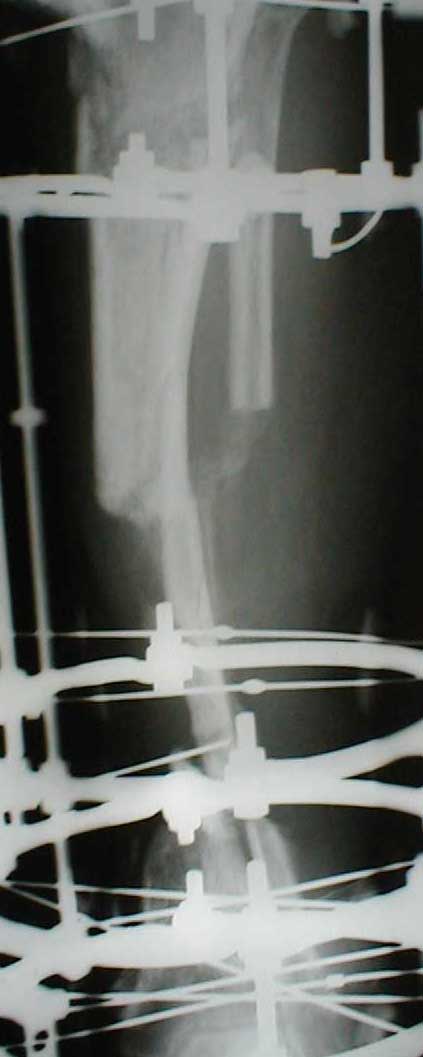

Может быть не совсем в тему, но... Скажите, а чем вызвана такая необычная компоновка аппарата: кольцевидный фиксатор и стержни? На первый взгляд так теряются преимущества монолатеральной стержневой фиксации (легкость перевязок) без достаточной компенсации достоинствами классического ВКДО Илизарова?

Re: Otkrity perelom (OI)

Андрей Крылов 02 Июнь 2005, 20:10

"Необычная" фиксация, предполагает осуществление максимальной стабильности проксимального фрагмента б\б кости. Как ее добиться - дело лечащего врача. При всем уважении к монолатеральным фиксаторам, лучше пожертвовать неудобствами при перевязках, чем нестабильностью фрагментов. Если поставлена цель сохранения конечности, то на данном этапе стабильность это - пункт № 1.

Отправитель: Ситник Александр 04 Июнь 2005, 10:59

Стабильность между фрагментами при дефекте около 10 см? Не слишком ли натянуто?

Отправитель: Dr. Castro 04 Июнь 2005, 20:11

Uvazaemy Dr. Alexander,

Ito vizvanno tem, chto, ja hotil dobitsa bistreshei stabilnoi fiksasii, chto bi dat' sosudestomu hirirgu vozmoznost' rabotat' po medialno-zadnoi poverhonoste, u menjia nibilo dostatochnoe vremjia, dla togo, chto bi provodit' spisy, ih natiagivat' i t.d. i t.p. pre itom ja ni narushal prinsepov vneshnei fikasii dla fixasii poddobnih perelomov. U manjia bili pod rukoi fixatory Hoffmana, i drugie unilateral fixatores, no ja ni stal imi polzovatsa, potomuchto, na moi vzglad', oni malo effectivnie dla dannogo vida povrezdenjia, t.k., oni sozdaiot bol'shoi richag, v rezultate- ita vliaet na stabil'nost', ossobenno v distalnih otdelah, ito kak pravilo, prevodit' k zametnomu oteku nize pereloma, a tut mi smogli provodit'sterzny v teh ploskostiah, kororie nam udobnie v udobnih mestah sobludjia prinsepov "bistro, stabilno, minimalno"

Malo togo, Unilateral frames, ni sposobnie k dalnishemu razvetio, i rano ili pozdno predetsa perehodit' na Ring fixators, tak, chto luche iz nih i nachinat', a voprochem, u kazdego vracha est' vsai vzglady i biomechanicheskie soobrazenjia na opredelennio temu, u opredellnogo bolnogo, i ni vazno kakogo sveta koshky, i vazno chto ona lovit' mish'.